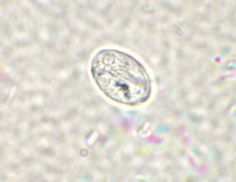

GIARDIA LAMBLIA Tsüst (4 tuumaga) Fekaaläigepreparaat